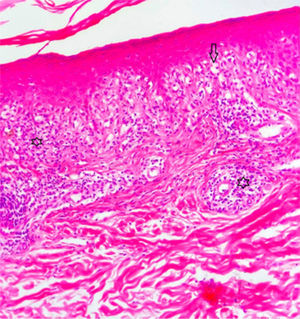

A 42-year-old woman presented with pruritic lesions that had appeared over the course of 5 months. Skin examination showed extensive areas of erythematous-purple lichenoid papules and plaques on the trunk and extremities (Fig. 1A–C). The oral and genital mucosa and nails were normal. The patient reported that she had been diagnosed with PCR-confirmed COVID-19 just 10 days before the lesions had appeared. She had not been hospitalized for COVID-19, but did receive treatment with favipiravir and analgesics. The information provided was confirmed by consulting the local COVID-19 database. The infection subsided within 5 days, and the skin lesions began to appear shortly afterwards. The patient did not consult a doctor, as she hoped that the lesions would disappear on their own. The relationship between COVID-19 and the skin lesions was not therefore recorded at the time, which is a weakness of this report. The differential diagnosis included lichen planus, lichenoid drug eruption, PLC, atypical pityriasis rosea, and prurigo. Histopathologic examination showed hyperkeratosis, irregular acanthosis, focal spongiosis, lymphocyte exocytosis in the epidermis, and a band-like lymphocytic infiltrate and melanophages in the superficial dermis (Fig. 2). Based on the clinical and histologic findings, the patient was diagnosed with PLC and treated with oral doxycycline, topical corticosteroids, and emollients. The lesions did not improve after 1 month of doxycycline, and the patient was started on narrowband UV-B therapy.